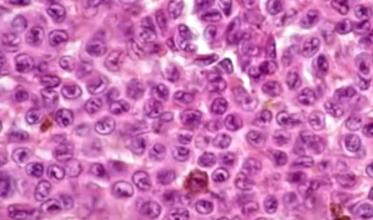

- Le Data Challenge CYTOLOGIA x Sommet pour l’action sur l’IA : porté par le Groupe Francophone d’Hématologie Cellulaire en partenariat avec Algoscope, le challenge portait sur l’analyse de plus de 70 000 images de leucocytes normaux et pathologiques issus de frottis sanguins. L’objectif du défi était de faire émerger des solutions fiables et accessibles pour automatiser l’analyse et la classification des leucocytes et ainsi permettre de proposer un diagnostic rapide et exact aux patients, peu importe leur localisation géographique.

A l’issue de 6 semaines de compétition où près de 250 équipes du monde entier se sont affrontées, plus de 2 000 modèles ont été soumis et les trois meilleurs ont atteint des scores dépassant 93 % de précision. Les modèles récompensés sont disponibles en open source.

Le Data Challenge Cytologia et ses résultats ont été mis à l’honneur à l’occasion du Sommet pour l’action sur l’intelligence artificielle qui a eu lieu à Paris en février 2025.

Découvrez plus en détail les lauréats et leurs résultats via le replay de la Journée de l’open science en santé du 4 juin 2025.